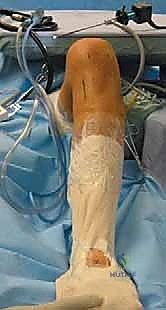

5. الكسور الانقلاعية (Avulsion Fractures): حيث يحتاج العظم المنفصل إلى تثبيت فوري بالمسامير.